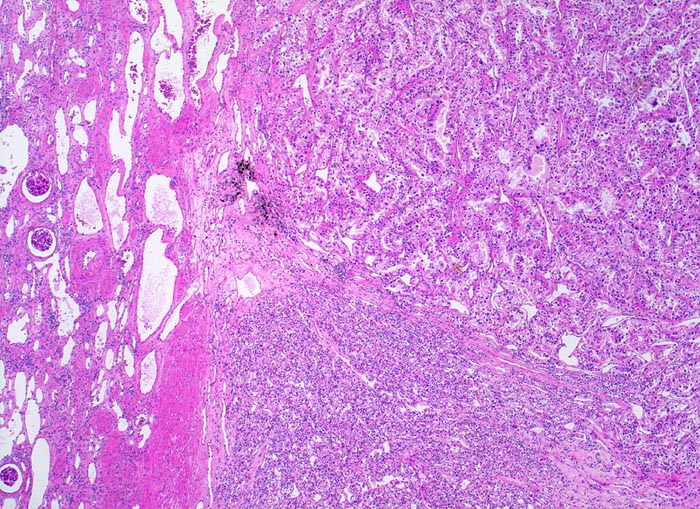

• Saum von komprimiertem und fibrosiertem Nierenparenchym unmittelbar angrenzend an das Karzinom (makroskopisch als Pseudokapsel imponierend). Übriges nicht-neoplastisches Restnierenparenchym mit leichter tubulointerstitieller Fibrose und Atrophie.

• Expansiv wachsender, scharf begrenzter knotiger Tumor ohne Durchbruch der Nierenkapsel.

• Solide Tumorzellaggregate eingefasst von dünnen Bindegewebssepten mit zahlreichen dünnwandigen Blutgefässen.

• Frische intratumorale Einblutungen und Blutungsresiduen (Siderinpigment)